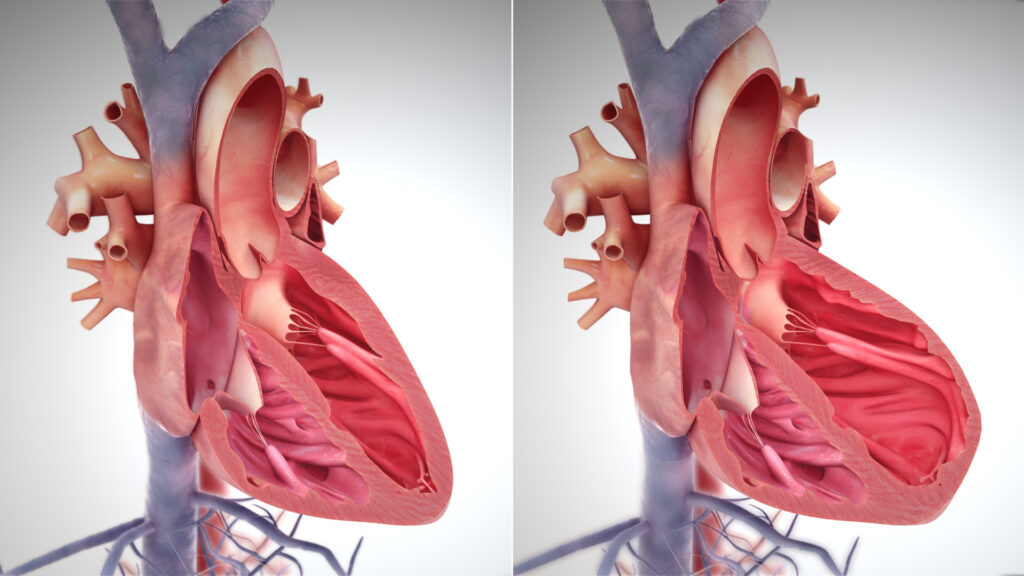

La disfunzione può essere di natura strutturale, coinvolgendo alterazioni macroscopiche come la dilatazione delle camere o l’ipertrofia delle pareti, oppure funzionale, riguardando anomalie nel ciclo contrattile (sistole) o nel rilassamento e riempimento (diastole).3 4

Meccanismo di Frank-Starling e ipertrofia

Il rimodellamento strutturale segue la legge di Laplace. Per ridurre lo stress di parete dovuto all’aumento della pressione o del raggio della camera, il cuore aumenta lo spessore delle pareti (ipertrofia):

- ipertrofia eccentrica: causata da sovraccarico di volume. I sarcomeri si aggiungono in serie, portando a una dilatazione della camera con spessore di parete che può rimanere normale o ridursi proporzionalmente;

- ipertrofia concentrica: causata da sovraccarico di pressione. I sarcomeri si aggiungono in parallelo, le pareti si ispessiscono e il volume della camera diminuisce.